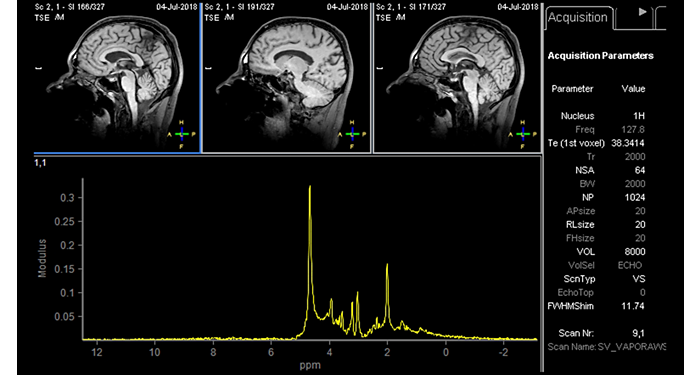

El 70% de los radiólogos consideran que las indicaciones neurológicas son un desafío, sobre todo debido a la falta de técnicas apropiadas de imagenología y visualización¹. Philips tiene como objetivo proporcionar la mejor claridad de diagnóstico posible y orientación terapéutica para todos los pacientes con trastornos neurológicos. Al aprovechar nuestra plataforma digital dStream, este año presentamos un conjunto de estrategias nuevas de imagenología y visualización. Esto puede ayudarlo a resolver preguntas sobre neurología complejas con mayor certeza, así como a desbloquear nuevos territorios neurológicos en aplicaciones neurofuncionales avanzadas. Este es un paso clave para aumentar el diagnóstico neurológico y, en última instancia, impactar más vidas con la RM. ¹ TMTG Market Survey 2016

Nuevas aplicaciones neurológicas